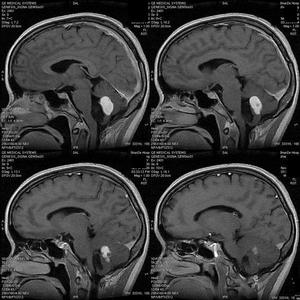

4.MRI MRI是診斷脂肪瘤最好的方法。T1加權像及T2加權像上均呈高信號脂肪瘤壁上的鈣化有時呈無信號影。

大腦半球間裂(胼胝體)脂肪瘤的MRI可顯示:①位於中線幾乎對稱的脂肪腫塊,占據半球間裂的局部區域,通常在胼胝體附近;②在胼胝體壓部周圍示不同程度的延展,經脈絡裂到脈絡叢,沿大腦裂分布;③37%~50%同時伴有胼胝體發育不良;④11%同時伴有皮下脂肪瘤;⑤包圍半球間動脈使其形成梭狀擴張;⑥脂肪瘤外周殼狀鈣化或其中含緻密骨。